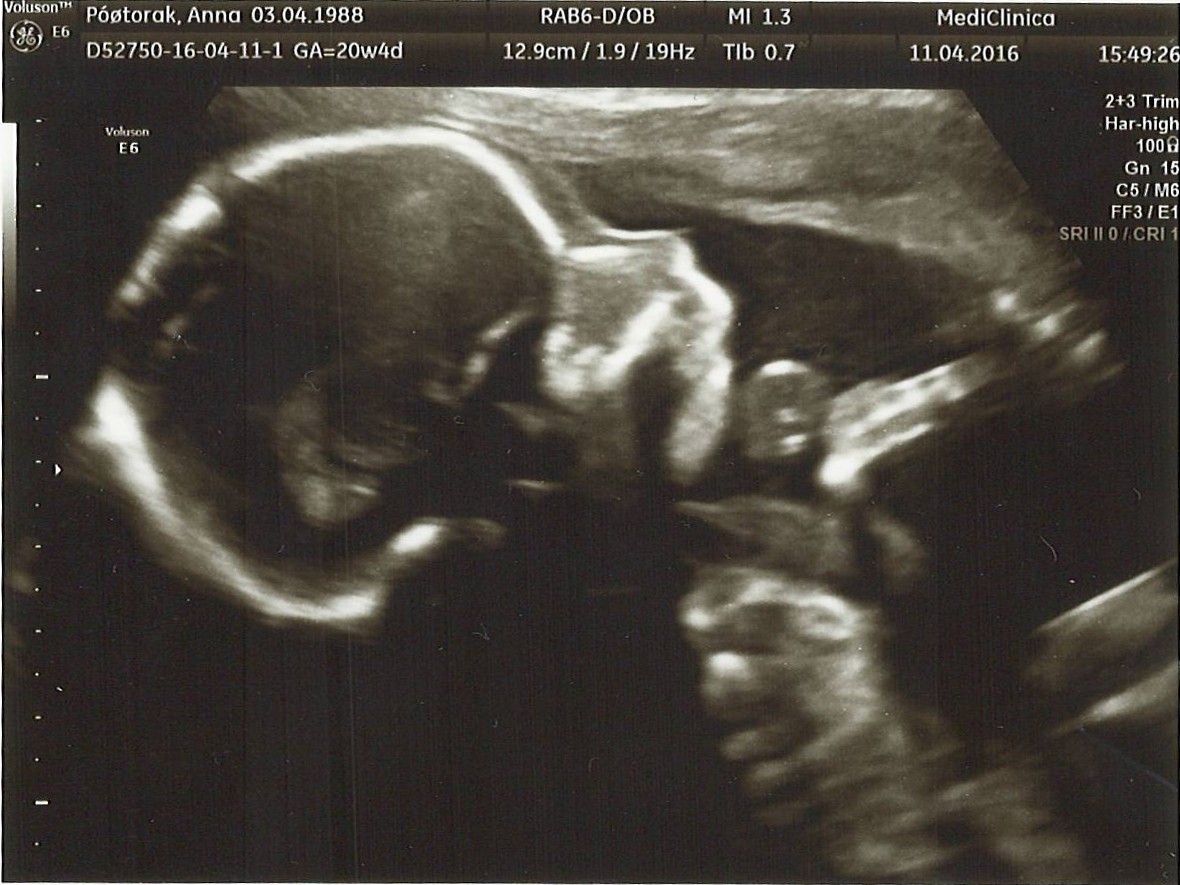

jestem po usg- na 100000% CHŁOPAK wiec dominika prosze o wpisanie :)

658 gram w 23 tyg 5 dni.

wszytsko ok